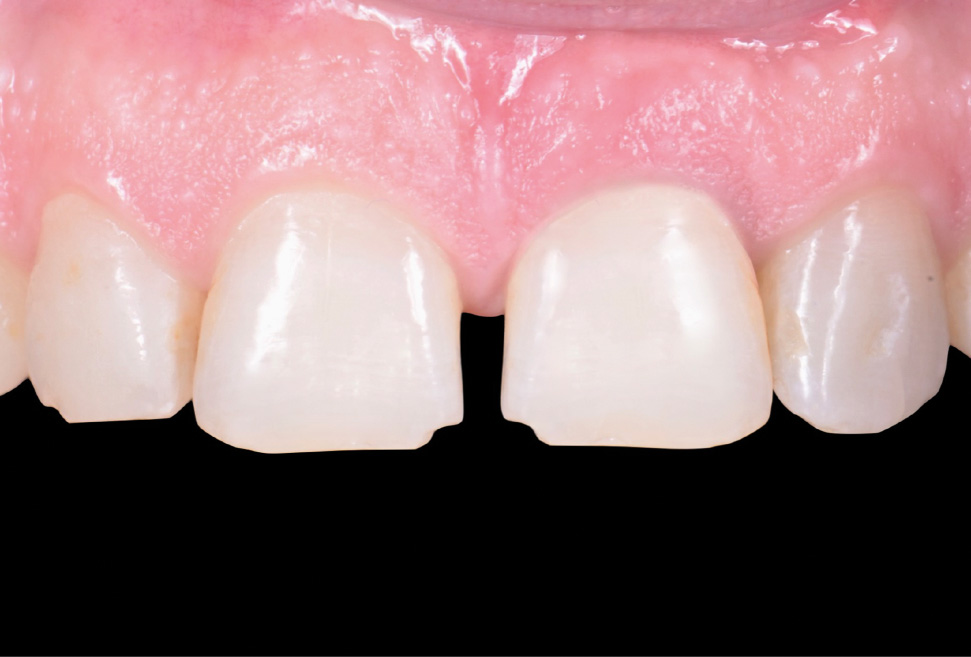

A questo punto, il provvisorio è stato rimosso e rifinito in modo da creare un profilo di emergenza che sostenesse il tessuto innestato e poi consegnato (fig.13, 14).

A 4 mesi dall’inserimento implantare il provvisorio è stato rimosso e si è potuto apprezzare la perfetta maturazione dei tessuti (fig.15).

Il tecnico, per creare il design della corona definitiva, ha utilizzato il design del provvisorio precedentemente creato, unendolo al profilo di emergenza creato nell’immediato post chirurgico. È stata quindi creata una corona in zirconia con colorazione superficiale incollata ad abutment in titanio che è stata successivamente serrata al pilastro intermedio (fig.17,18).